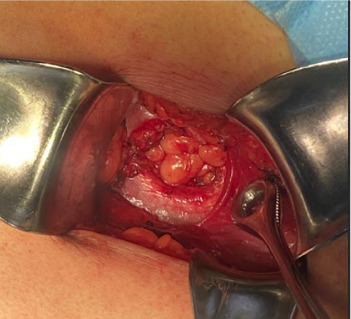

背景:Grynfelt 腰疝是所有腹壁疝中最罕见的一种,占病例的 1.5% 到 2%,迄今为止仅描述过 300 到 350 例。腰疝可以是先天性的,也可以是后天性的,通常由外伤或手术(先天性)引发。诊断依据临床表现,并通过计算机断层扫描确诊。需要进行手术治疗,通过开腹或腹腔镜手术进行修补。材料与方法:本病例为一名年轻女性,既往无手术史,也无外伤史,诊断为 Grynfelt 疝。手术结果患者接受了选择性左腰部切除手术,并使用腹膜上聚丙烯网片进行了疝成形术。术后恢复良好,术后 4 小时即可出院。普外科门诊分别在 20 天、1 个月、3 个月和 6 个月进行了随访,没有发现复发、并发症或事故。结论Grynfelt疝是一种罕见病,需要高度怀疑才能准确诊断。虽然病例通常没有症状,但未经治疗的疝气可导致严重的发病率。早期识别和及时手术治疗对于缓解症状和预防并发症至关重要。在本病例报告中,手术治疗包括通过左腰部切开术进行疝成形术,修补疝缺损并缩小疝内容物。为确保充分闭合,还放置了上腹膜网片。鉴于这种病症的罕见性,文献中没有具体的治疗指南。因此,这种类型的修补术是根据术中发现决定的。需要进一步开展研究,以明确管理策略,优化 Grynfelt 疝患者的治疗效果。

Background: Grynfelt's lumbar hernia is the rarest of all abdominal wall hernias, accounting for between 1.5% and 2% of cases, with only 300-350 instances described to date. Lumbar hernias can be congenital or acquired, often triggered by trauma or surgery (iatrogenic). Diagnosis is clinical and confirmed via computed tomography. Surgical intervention is required for resolution, with repair performed either through open or laparoscopic surgery. Material and Methods: We present the case of a young female with no prior surgical or traumatic history, in whom the diagnosis of Grynfelt's hernia was made. Results: The patient underwent elective left lumbotomy surgery with hernioplasty using a supra-aponeurotic polypropylene mesh. Postsurgical recovery was adequate, and she was discharged 4 h after surgery. Follow-up in the general surgery outpatient clinic occurred at 20 days, 1, 3, and 6 months, with no recurrence, complications, or incidents. Conclusion: Grynfelt's hernia is a rare entity that requires a high index of suspicion for accurate diagnosis. Although cases are often asymptomatic, untreated hernias can lead to significant morbidity. Early recognition and timely surgical intervention are crucial for symptom relief and prevention of complications. In this case report, surgical management involved hernioplasty through a left lumbotomy approach, repairing the hernia defect and reducing the hernia content. Supra-aponeurotic mesh was placed to ensure adequate closure. Given the rarity of this pathology, no specific management guidelines exist in the literature. Therefore, the decision for this type of repair was based on intraoperative findings. Further research is needed to clarify management strategies and optimize outcomes for patients with Grynfelt's hernia.